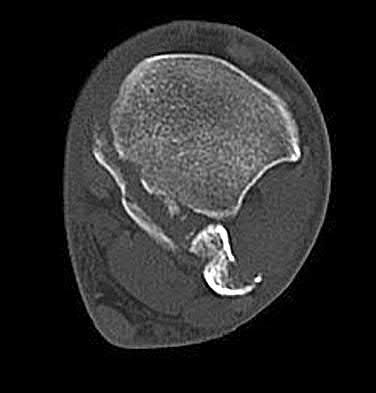

A 28-year-old male sustains a severe hyper-dorsiflexion injury to his ankle in a motor vehicle accident, resulting in a Hawkins Type III talar neck fracture. Which of the following arteries provides the predominant blood supply to the body of the talus, placing it at significant risk for avascular necrosis in this injury?

Options:

Correct Answer: Artery of the tarsal canal

Explanation:

The artery of the tarsal canal, which is a branch of the posterior tibial artery, provides the dominant blood supply to the talar body. In a Hawkins Type III fracture (talar neck fracture with subtalar and tibiotalar dislocation), the blood supply from the artery of the tarsal canal, the artery of the sinus tarsi, and capsular vessels are disrupted, leading to an avascular necrosis (AVN) rate approaching 100%.